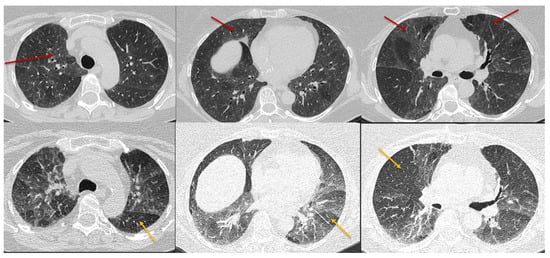

| Typical HP Pattern (Suggests a Diagnosis of HP) | Compatible with HP | Indeterminate for HP |

| At least one finding indicative of small airway disease | Not applicable | |

| Air trapping | ||

| Ill-defined <5 mm centrilobular nodules | ||

| At least one finding indicative of parenchymal infiltration | ||

| Distribution of findings | ||

| Craniocaudal: diffuse +/− basal sparing | Craniocaudal: diffuse (variant: lower lobe predominance) | |

| Axial: diffuse | Axial: diffuse (variant: peribronchovascular) | |

| At least one finding indicative of small airway disease | At least one finding indicative of small airway disease | Neither Typical nor Compatible with HP |

| Three-density pattern | Three-density pattern | HRCT Patterns: UIP pattern Probably UIP pattern Indeterminate for UIP Fibrotic NSIP pattern OP like pattern Truly indeterminate pattern |

| Air trapping | Air trapping | |

| Ill-defined <5 mm centrilobular nodules | Ill-defined <5 mm centrilobular nodules | |

| At least one finding indicative of pulmonary fibrosis | Variant pattern of fibrosis | |

| Coarse reticulations with distortion | UIP pattern of fibrosis | |

| Traction bronchiectasis | Extensive GGO and superimposed subtle fibrosis | |

| Honeycombing (not dominant) | ||

| Distribution of findings | Variant distribution of fibrosis | |

| Random axially and craniocaudally | Craniocaudal: Upper lung zone predominant | |

| Mid zone predominant | Axial: peribronchovascular, subpleural | |

| Relative sparing of the bases |